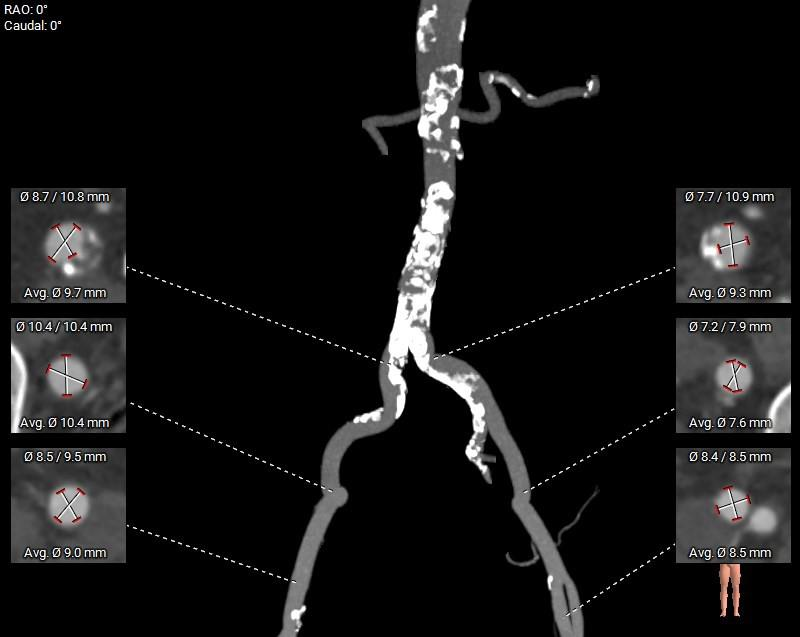

5.入路血管钙化严重,内径可,符合血管入路条件。

外周入路